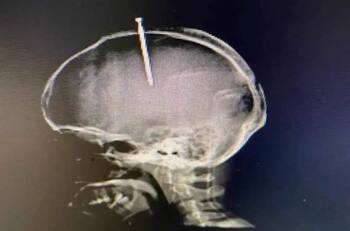

Un hombre, según reporta su familia, con serios problemas mentales, se enterró un clavo en su cabeza luego de "sentir su cerebro flojo". El sujeto actuó en un completo estado de alucinación, debido a un serio problema de adicción a las drogas. Su familia pide ayuda y teme por su vida.